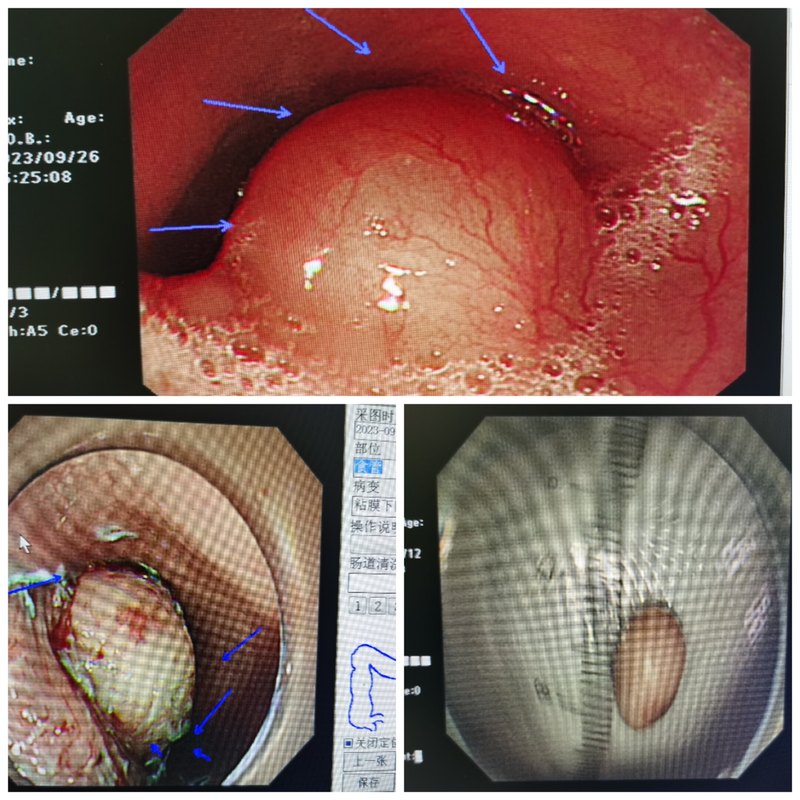

越来越多的健康人群开始重视胃肠镜体检,有些人拿到报告后,在胃镜检查报告中,发现有胃“SMT”的字样,很紧张,甚至以为自己得了什么绝症。今天,我们就简单来介绍一下胃SMT。SMT意思是消化道黏膜下肿瘤(SubMucosalTumor,SMT)。这是指一类来自消化道黏膜以下组织的肿块,包括起源于黏膜肌层、黏膜下层和固有肌层的肿瘤。它们在内镜下的表现形态相似,即表面覆有正常黏膜的隆起性病变,医生一般不取活检,因为活检取不到黏膜下的组织。发现SMT后,可能会被要求做个超声内镜(EndoscopicUltrasonography,EUS),有的时候会联合消化道增强CT,以确定肿瘤的来源层次、大小、质地及与周边组织血管的毗邻关系。上消化道的SMT以食管和胃最为常见,十二指肠较少见。最常见的上消化道SMT包括平滑肌瘤、间质瘤、神经内分泌肿瘤、脂肪瘤、颗粒细胞瘤、神经鞘瘤等。非肿瘤性病变的异位胰腺也会表现为SMT样。 胃黏膜下肿瘤发病率约十万分之一。患者很少有症状,大部分是因为体检胃镜无意中发现。如果肿瘤持续长大,影响食物通过或者表面有糜烂破溃时,则会出现疼痛、消化道出血等不适。那么发现了胃黏膜下肿瘤,到底是否需要切除呢,一般来说小于1cm的SMT,建议随访。当出现以下这些情况时,建议切除: 1)有症状(伴有出血、消化道梗阻等); 2)无症状但不断增大的黏膜下肿瘤; 3)明确是胃间质瘤(有恶性潜能,随直径增大恶性潜能增大); 4) 肿瘤大于2cm怀疑是胃间质瘤; 5) 性质不明确的黏膜下肿瘤,但是不能耐受或者因为焦虑不愿长期内镜检查随访。胃镜下手术创伤小,恢复快,是较小的黏膜下肿瘤治疗的优选(一般来说小于5cm的间质瘤,像平滑肌瘤更大也可以内镜下切除),可以完整切除后病理检查明确肿瘤性质内镜下的手术方式包括内镜黏膜下剥离术(ESD)、内镜黏膜下挖除术(ESE)、内镜全层切除术(EFTR)和内镜经黏膜下隧道肿瘤切除术(STER)。胃镜发现的SMT是胃癌吗?如何治疗?段本松 东方内镜 2024年07月27日17:40 上海 12人胃镜发现的SMT是胃癌吗?如何治疗?徐美东消化内镜工匠创新工作室科普系列文章越来越多的健康人群开始重视胃肠镜体检,有些人拿到报告后,在胃镜检查报告中,发现有胃“SMT”的字样,很紧张,甚至以为自己得了什么绝症。今天,我们就简单来介绍一下胃SMT。SMT意思是消化道黏膜下肿瘤(SubMucosalTumor,SMT)。这是指一类来自消化道黏膜以下组织的肿块,包括起源于黏膜肌层、黏膜下层和固有肌层的肿瘤。它们在内镜下的表现形态相似,即表面覆有正常黏膜的隆起性病变,医生一般不取活检,因为活检取不到黏膜下的组织。发现SMT后,可能会被要求做个超声内镜(EndoscopicUltrasonography,EUS),有的时候会联合消化道增强CT,以确定肿瘤的来源层次、大小、质地及与周边组织血管的毗邻关系。上消化道的SMT以食管和胃最为常见,十二指肠较少见。最常见的上消化道SMT包括平滑肌瘤、间质瘤、神经内分泌肿瘤、脂肪瘤、颗粒细胞瘤、神经鞘瘤等。非肿瘤性病变的异位胰腺也会表现为SMT样。 胃黏膜下肿瘤发病率约十万分之一。患者很少有症状,大部分是因为体检胃镜无意中发现。如果肿瘤持续长大,影响食物通过或者表面有糜烂破溃时,则会出现疼痛、消化道出血等不适。那么发现了胃黏膜下肿瘤,到底是否需要切除呢,一般来说小于1cm的SMT,建议随访。当出现以下这些情况时,建议切除: 1)有症状(伴有出血、消化道梗阻等); 2)无症状但不断增大的黏膜下肿瘤; 3)明确是胃间质瘤(有恶性潜能,随直径增大恶性潜能增大); 4) 肿瘤大于2cm怀疑是胃间质瘤; 5) 性质不明确的黏膜下肿瘤,但是不能耐受或者因为焦虑不愿长期内镜检查随访。胃镜下手术创伤小,恢复快,是较小的黏膜下肿瘤治疗的优选(一般来说小于5cm的间质瘤,像平滑肌瘤更大也可以内镜下切除),可以完整切除后病理检查明确肿瘤性质内镜下的手术方式包括内镜黏膜下剥离术(ESD)、内镜黏膜下挖除术(ESE)、内镜全层切除术(EFTR)和内镜经黏膜下隧道肿瘤切除术(STER)。接下来,我将结合我中心的实际临床病例,为大家介绍最常见的两种胃镜下发现的SMT:平滑肌瘤、间质瘤。01食管胃平滑肌瘤平滑肌瘤(Leiomyoma)是一种良性间叶肿瘤,具有平滑肌分化特征。胃镜发现的平滑肌瘤主要分布在食管和胃,尤其以食管为主,常见于食管胃交界处和食管中部。大多数患者无症状,当肿瘤增大时可能出现吞咽困难、疼痛或不适,常见的主诉包括胸骨后、剑突下或上腹部的疼痛或不适,以及上腹部饱胀感或压迫感。其他消化道非特异性症状包括食欲不振、反胃、嗳气、恶心和呕吐等。目前,内镜下对平滑肌瘤的诊断及处理已经非常成熟。病例1:食管平滑肌瘤患者女,37岁,外院胃镜检查发现食管距门齿35cm-37cm处有一黏膜下隆起,遂来我院行超声内镜检查。检查提示隆起处有均匀低回声团块,边界清晰,回声与固有肌层连续,截面大小约2.02.0cm,结合CT报告考虑平滑肌瘤可能。我中心决定采用内镜经黏膜下隧道肿瘤切除术(STER)进行肿瘤切除,手术顺利取出大小约2.5cm的平滑肌瘤。病例2:胃近贲门平滑肌瘤患者女,55岁,1年前当地医院胃镜检查发现胃底黏膜下隆起,未予重视,未服药及规范随访。近日复查内镜发现胃底黏膜下隆起较之前增大,遂来我院诊治。CT提示贲门占位,大小约4.0cm。结合超声胃镜结果,考虑贲门SMT,平滑肌瘤可能。我中心决定采用STER进行肿瘤切除,手术顺利,取出大小约4.0cm的马蹄样平滑肌瘤。胃镜发现的SMT是胃癌吗?如何治疗?段本松 东方内镜 2024年07月27日17:40 上海 12人胃镜发现的SMT是胃癌吗?如何治疗?徐美东消化内镜工匠创新工作室科普系列文章越来越多的健康人群开始重视胃肠镜体检,有些人拿到报告后,在胃镜检查报告中,发现有胃“SMT”的字样,很紧张,甚至以为自己得了什么绝症。今天,我们就简单来介绍一下胃SMT。SMT意思是消化道黏膜下肿瘤(SubMucosalTumor,SMT)。这是指一类来自消化道黏膜以下组织的肿块,包括起源于黏膜肌层、黏膜下层和固有肌层的肿瘤。它们在内镜下的表现形态相似,即表面覆有正常黏膜的隆起性病变,医生一般不取活检,因为活检取不到黏膜下的组织。发现SMT后,可能会被要求做个超声内镜(EndoscopicUltrasonography,EUS),有的时候会联合消化道增强CT,以确定肿瘤的来源层次、大小、质地及与周边组织血管的毗邻关系。上消化道的SMT以食管和胃最为常见,十二指肠较少见。最常见的上消化道SMT包括平滑肌瘤、间质瘤、神经内分泌肿瘤、脂肪瘤、颗粒细胞瘤、神经鞘瘤等。非肿瘤性病变的异位胰腺也会表现为SMT样。 胃黏膜下肿瘤发病率约十万分之一。患者很少有症状,大部分是因为体检胃镜无意中发现。如果肿瘤持续长大,影响食物通过或者表面有糜烂破溃时,则会出现疼痛、消化道出血等不适。那么发现了胃黏膜下肿瘤,到底是否需要切除呢,一般来说小于1cm的SMT,建议随访。当出现以下这些情况时,建议切除: 1)有症状(伴有出血、消化道梗阻等); 2)无症状但不断增大的黏膜下肿瘤; 3)明确是胃间质瘤(有恶性潜能,随直径增大恶性潜能增大); 4) 肿瘤大于2cm怀疑是胃间质瘤; 5) 性质不明确的黏膜下肿瘤,但是不能耐受或者因为焦虑不愿长期内镜检查随访。胃镜下手术创伤小,恢复快,是较小的黏膜下肿瘤治疗的优选(一般来说小于5cm的间质瘤,像平滑肌瘤更大也可以内镜下切除),可以完整切除后病理检查明确肿瘤性质内镜下的手术方式包括内镜黏膜下剥离术(ESD)、内镜黏膜下挖除术(ESE)、内镜全层切除术(EFTR)和内镜经黏膜下隧道肿瘤切除术(STER)。接下来,我将结合我中心的实际临床病例,为大家介绍最常见的两种胃镜下发现的SMT:平滑肌瘤、间质瘤。01食管胃平滑肌瘤平滑肌瘤(Leiomyoma)是一种良性间叶肿瘤,具有平滑肌分化特征。胃镜发现的平滑肌瘤主要分布在食管和胃,尤其以食管为主,常见于食管胃交界处和食管中部。大多数患者无症状,当肿瘤增大时可能出现吞咽困难、疼痛或不适,常见的主诉包括胸骨后、剑突下或上腹部的疼痛或不适,以及上腹部饱胀感或压迫感。其他消化道非特异性症状包括食欲不振、反胃、嗳气、恶心和呕吐等。目前,内镜下对平滑肌瘤的诊断及处理已经非常成熟。病例1:食管平滑肌瘤患者女,37岁,外院胃镜检查发现食管距门齿35cm-37cm处有一黏膜下隆起,遂来我院行超声内镜检查。检查提示隆起处有均匀低回声团块,边界清晰,回声与固有肌层连续,截面大小约2.02.0cm,结合CT报告考虑平滑肌瘤可能(图1)。我中心决定采用内镜经黏膜下隧道肿瘤切除术(STER)进行肿瘤切除,手术顺利取出大小约2.5cm的平滑肌瘤(图2)。病例2:胃近贲门平滑肌瘤患者女,55岁,1年前当地医院胃镜检查发现胃底黏膜下隆起,未予重视,未服药及规范随访。近日复查内镜发现胃底黏膜下隆起较之前增大,遂来我院诊治。CT提示贲门占位,大小约4.0cm。结合超声胃镜结果,考虑贲门SMT,平滑肌瘤可能(图3)。我中心决定采用STER进行肿瘤切除,手术顺利,取出大小约4.0cm的马蹄样平滑肌瘤(图4)。02胃肠道间质瘤胃肠道间质瘤(GIST)是消化道最常见的间叶源性肿瘤,约占全消化道肿瘤的3%。在消化道中,以胃最为常见,其他部位较少见。因此,胃镜下发现的间质瘤大多位于胃部。该肿瘤可发生于任何年龄。男女发病差异不明显。早期多无症状,由于其球状非侵袭性的生长方式,即便肿瘤较大也不一定产生压迫感和出血,是一种很难在早期发现的隐形杀手。随着内镜检查的普及和技术进步,早期发现和超级微创治疗GIST已经成为可能。内镜下的超级微创手术治疗GIST不仅创伤小、痛苦少、操作时间短、并发症少,还能提供完整的病理学诊断资料,以便制定预后和随访策略。病例3:胃底间质瘤患者女,76岁,半年前体检时胸部CT平扫提示胃底可疑占位。病程中,患者偶有反酸,无其他不适。再次复查胸部CT提示胃底可疑占位,超声胃镜显示病灶呈均匀低回声,边界清楚,起源于固有肌层,大小约26mm24mm,结合CT报告考虑间质瘤伴钙化可能。我中心决定采用内镜全层切除术(EFTR)进行肿瘤切除,手术顺利取出大小约3.5cm的间质瘤。总之,胃镜检查发现胃SMT后,无需过分紧张,需要寻求专业的内镜医生意见,随访或内镜下切除,如果较大无法内镜下切除则需要考虑外科手术治疗。